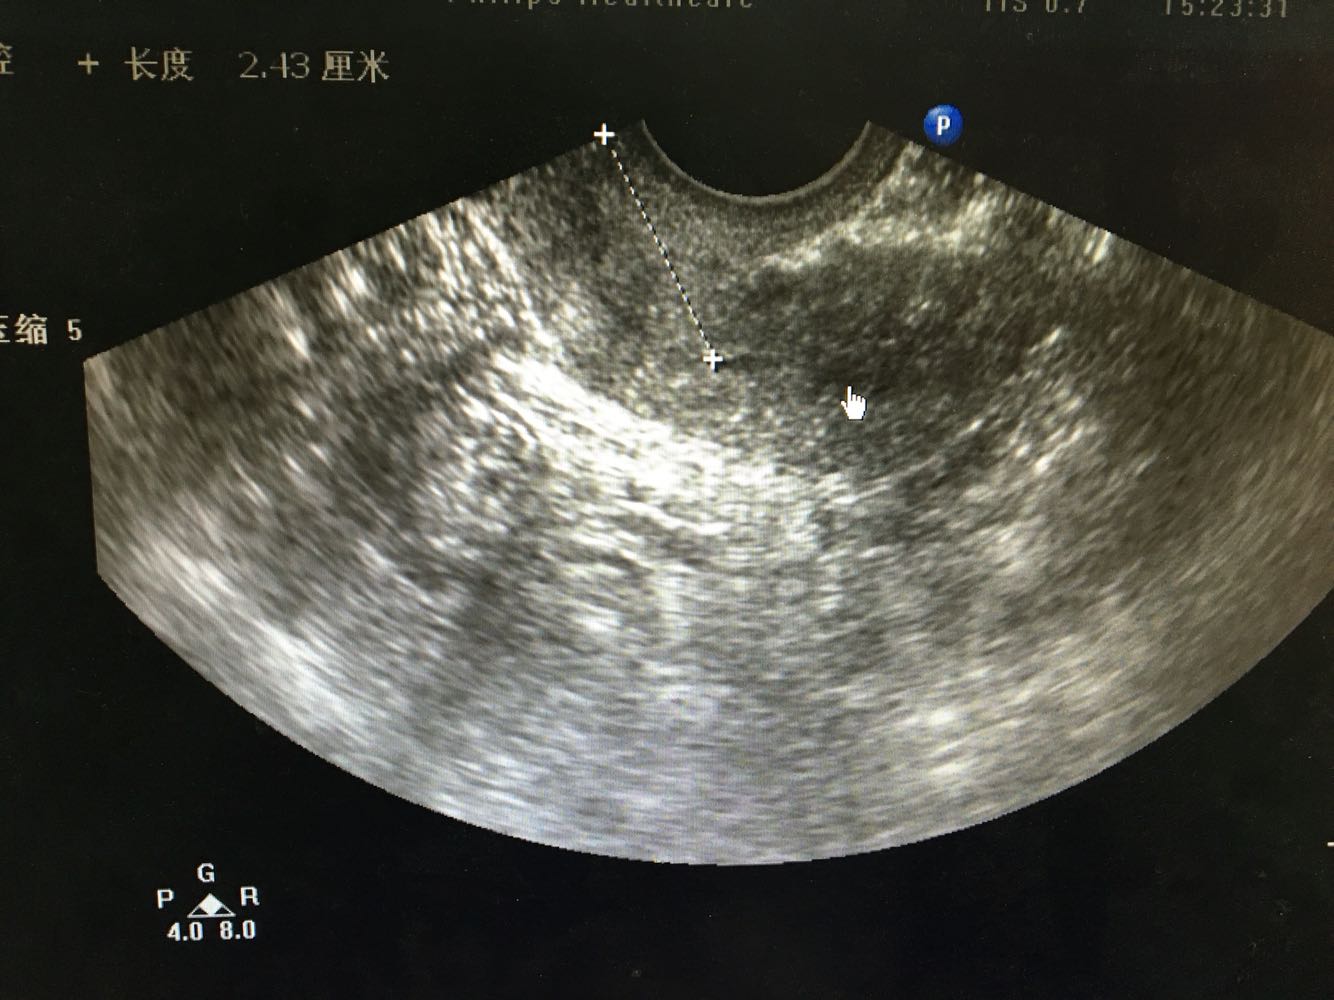

1、患者,女,70岁   2、主诉:发现外阴肿物6月余,进行性加重伴排尿困难2月余  3、现病史:2-0-1-2,18岁 5/25天,经期规则,量中,痛经(-),50岁时绝经。患者于6月前发现阴道口脱出物,当时无腹痛,无尿频尿急,无大便改变,至医院就诊,诊断为子宫脱垂,可还纳,建议提肛等物理治疗,症状未改善。2月前患者自觉阴道口脱出物块感明显 ,有尿频尿急,排尿困难,大便正常,无腹痛。患者未至医院就诊,1月前患者排尿困难进行性加重,伴要不酸痛及下坠感,站立过久及劳累后症状加重,且站立阴道脱出物表面有污秽物,拭去后少量出血。遂至我院就诊,查超声示右附件囊肿,子宫肌瘤。现为求进一步治疗,拟“子宫脱垂II度重”收治入院。患者自患病以来神清,精神佳,胃纳可,夜眠可,有尿频尿急及排尿困难,大便正常,体重无明显变化。

4、妇科检查:外阴:已婚产式阴道:前壁膨出阴道口宫颈:肥大,轻糜 ,突出于阴道口。子宫:萎缩,部分脱出阴道口附件:双侧附件(-)      5、辅助检查: